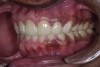

A thorough clinical examination and analysis were carried out to assess the esthetic and functional problems of the patient (Figure 2 through Figure 7). The medical history was non-contributory, except for mild leukoderma. Temporomandibular joint (TMJ) function was within normal range.

Figure 2. Preoperative 1:2 retracted frontal view.

Figure 2

Figure 3. Preoperative 1:2 retracted right lateral view.

Figure 3

Figure 4. Preoperative 1:2 retracted left lateral view.

Figure 4

Figure 5. Preoperative 1:1 retracted frontal view.

Figure 5

Figure 6. Preoperative maxillary occlusal view.

Figure 6

Figure 7. Preoperative mandibular occlusal view.

Figure 7